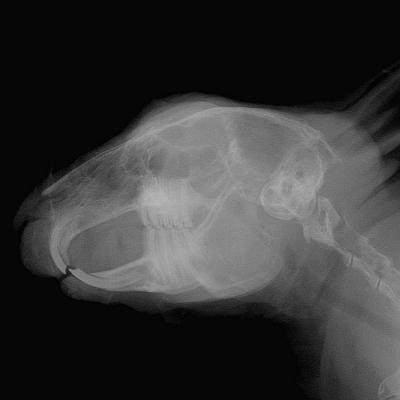

Radio d'une tête de Lapin